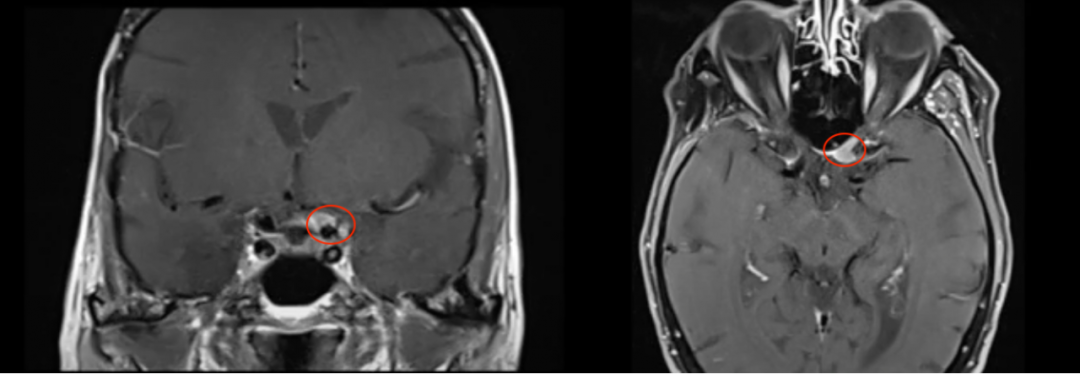

53岁男性,2012年出现V1(嗅神经)和V2(视神经)感觉减退,查出右侧Meckel’s腔脑膜瘤进行手术,术后病理结果为WHO 2级。7年后,脑膜瘤复发,再次出现严重的V1(嗅神经)、V2(视神经)和V3(动眼神经)感觉减退和疼痛。磁共振成像(MRI)显示肿瘤大面积复发,延伸至海绵窦(CS)、后颅窝(PF)、蝶窦(SS)、翼腭窝(PPF)和颞下窝(ITF)。

术前术后影像对比:肿瘤得到完全切除

术后情况:角膜炎在10天内消退,国际卫生组织II级脑膜瘤(已确诊),V3感觉减退在2个月后得到好转。